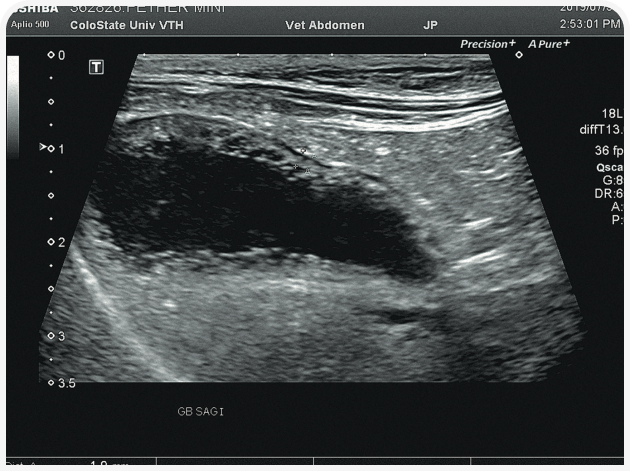

В этом случае для диагностики целесообразно провести ультразвуковое исследование органов брюшной полости, причем важно не столько то, что оно покажет (неспецифические изменения печени и лимфаденопатия), сколько то, чего оно не покажет. В нашем примере в желчном пузыре и желчных путях патологии, скорее всего, выявлено не будет.

Решающее значение для диагностики и лечения в этом случае будет иметь ультразвуковое исследование органов брюшной полости (Рисунок 6). Диагностику триадита у кошек облегчают визуализация поджелудочной железы и определение толщины/архитектоники стенки кишечника; изменения в паренхиме печени по-прежнему остаются неспецифичными, но изменения в желчном пузыре, скорее всего, помогут установить диагноз. При нейтрофильном холангите у кошки результаты визуализации желчных путей могут оказаться нормальными, но во многих случаях стенка желчного пузыря будет утолщенной и неровной, даже зубчатой (Рисунок 7) (22). Возможны осадок (Рисунок 8) или наличие камней в желчном пузыре, поэтому желчевыводящие пути важно просмотреть до двенадцатиперстной кишки, чтобы исключить внепеченочную окклюзию желчных протоков. Во многих случаях общий желчный проток оказывается перекрыт. Возможен асцит, и в этом случае оправдано проведение аспирации и анализа состава жидкости.